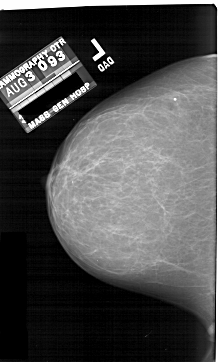

A_1690_1.RIGHT_MLO

RIGHT_MLO LINES 6871 PIXELS_PER_LINE 4396 BITS_PER_PIXEL 12 RESOLUTION 43.5 OVERLAY

FILE: A_1690_1.RIGHT_MLO.OVERLAY

TOTAL_ABNORMALITIES 1

ABNORMALITY 1

LESION_TYPE CALCIFICATION TYPE AMORPHOUS DISTRIBUTION CLUSTERED

ASSESSMENT 4

SUBTLETY 4

PATHOLOGY BENIGN